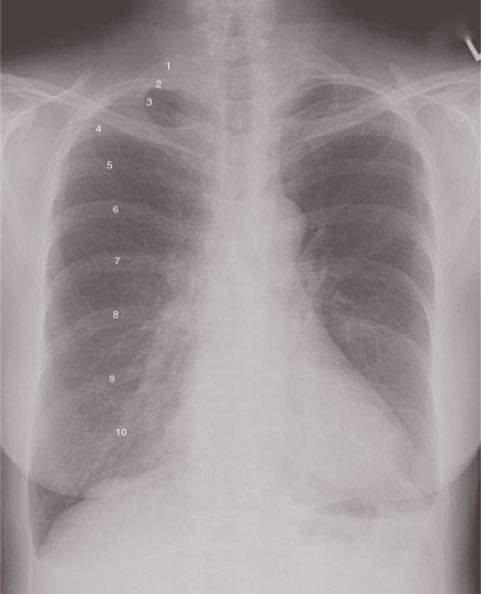

Which of the following criteria are used to evaluate a PA projection of the chest?

1.Ten posterior ribs should be visualized.

2.Sternoclavicular joints should be symmetrical.

3.The scapulae should be lateral to the lung fields.

A 1 and 2 only

B 1 and 3 only

C 2 and 3 only

D 1, 2, and 3

-To evaluate sufficient inspiration and lung expansion, 10 posterior ribs should be visualized. The sternoclavicular joints should be symmetrical; any loss of symmetry indicates rotation. To visualize maximum lung area, the shoulders are rolled forward to move the scapulae laterally from the lung fields.